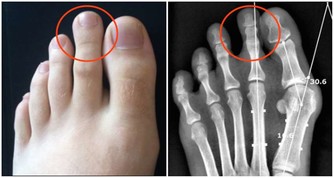

而缺乏維生素B6時,人的口唇、舌頭可能會有腫痛感,手指、腳趾還可能出現酥麻的刺痛感。